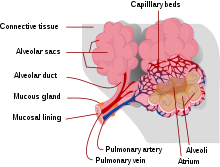

Interstitial lung disease affects gas flow in the alveoli

The alveoli

Interstitial lung disease (ILD), or diffuse parenchymal lung disease (DPLD),[3] is a group of respiratory diseases affecting the interstitium (the tissue and space around the alveoli (air sacs) of the lungs.[4] It concerns alveolar epithelium, pulmonary capillary endothelium, basement membrane, and perivascular and perilymphatic tissues. It may occur when an injury to the lungs triggers an abnormal healing response. Ordinarily, the body generates just the right amount of tissue to repair damage, but in interstitial lung disease, the repair process is disrupted, and the tissue around the air sacs (alveoli) becomes scarred and thickened. This makes it more difficult for oxygen to pass into the bloodstream. The disease presents itself with the following symptoms: shortness of breath, nonproductive coughing, fatigue, and weight loss, which tend to develop slowly, over several months. The average rate of survival for someone with this disease is between three and five years.[5] The term ILD is used to distinguish these diseases from obstructive airways diseases.